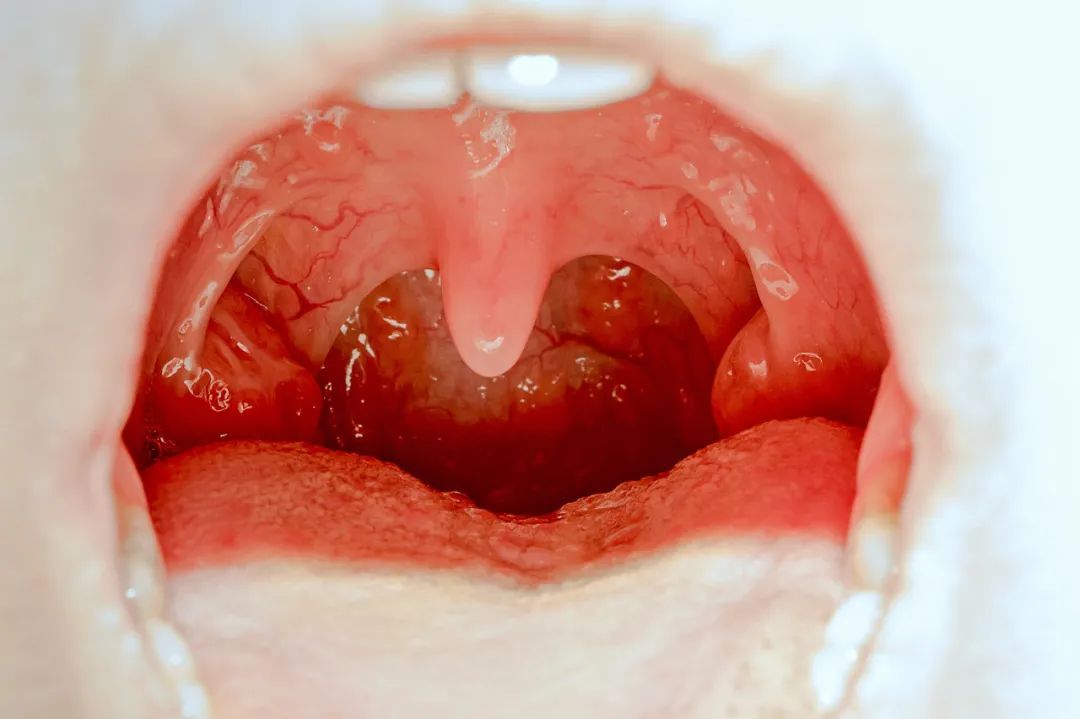

扁桃体作为咽喉部位的椭圆形腺体,分为左右两侧,是人体末梢免疫器官的一部分,对儿童有一定免疫功能。它能保护呼吸道和消化道,避免细菌侵入,还能产生免疫抗体。

扁桃体可以说是人身上最“作”的器官,没有之一。为什么?因为慢性扁桃体炎会导致咽干、异物感、发痒等。急性扁桃体炎可有咽痛,低热,疲劳,食欲欠佳等。化脓性扁桃体炎发病很急,全身症状重,发热,畏寒,食欲不振,体温可升至38℃~40℃,局部表现咽痛明显,甚至饮食、语言困难。因此,有人说,切了就没事了。真的可以一切了事吗?那可不一定。扁桃体曾为我们抵御各种细菌立下过汗马功劳。